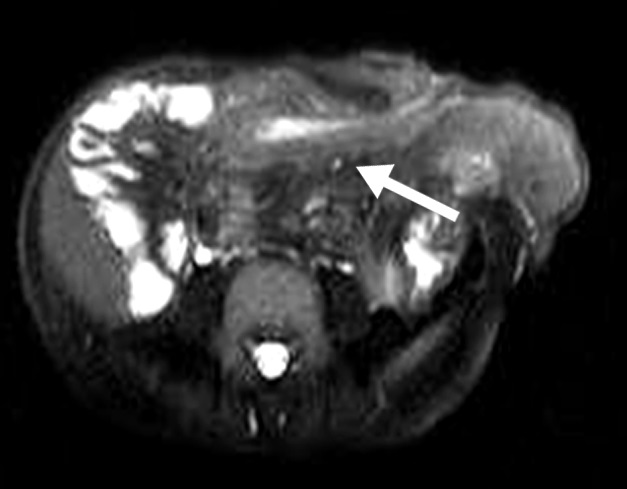

Figura 3

Enfermedad de Crohn

a) Secuencia T2 axial sin

supresión grasa evidencia

engrosamiento parietal de la

última asa ileal (flecha blanca).

b y c) secuencias T1 con

saturación grasa y gadolinio.

Realce estrajpgicado dado

por realce de la mucosa

(flecha larga) y serosa (flecha

corta) separadas por la

capa submucosa edematosa

(asterisco).